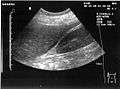

A normal ultrasonographic view of Morison's pouch. The bright line is the capsule of the kidney; there is no fluid present and hence no visible space.

Ultrasound of liver (left side of the image) and right kidney (right side of the image) and Morison's pouch, not containing fluid.- Abdominal CT, showing Morison's pouch as the dark margin surrounding the right kidney (at lower left corner of image).